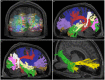

The human inferior longitudinal fasciculus (ILF) is a ventral, temporo-occipital association tract. Though described in early neuroanatomical works, its existence was later questioned. Application of in vivo tractography to the neuroanatomical study of the ILF has generally confirmed its existence, however, consensus is lacking regarding its subdivision, laterality and connectivity. Further, there is a paucity of detailed neuroanatomic data pertaining to the exact anatomy of the ILF. Generalized Q-Sampling imaging (GQI) is a non-tensor tractographic modality permitting high resolution imaging of white-matter structures. As it is a non-tensor modality, it permits visualization of crossing fibers and accurate delineation of close-proximity fiber-systems. We applied deterministic GQI tractography to data from 30 healthy subjects and a large-volume, averaged diffusion atlas, to delineate ILF anatomy. Post-mortem white matter dissection was also carried out in three cadaveric specimens for further validation. The ILF was found in all 60 hemispheres. At its occipital extremity, ILF fascicles demonstrated a bifurcated, ventral-dorsal morphological termination pattern, which we used to further subdivide the bundle for detailed analysis. These divisions were consistent across the subject set and within the atlas. We applied quantitative techniques to study connectivity strength of the ILF at its anterior and posterior extremities. Overall, both morphological divisions, and the un-separated ILF, demonstrated strong leftward-lateralized connectivity patterns. Leftward-lateralization was also found for ILF volumes across the subject set. Due to connective and volumetric leftward-dominance and ventral location, we postulate the ILFs role in the semantic system. Further, our results are in agreement with functional and lesion-based postulations pertaining to the ILFs role in facial recognition.